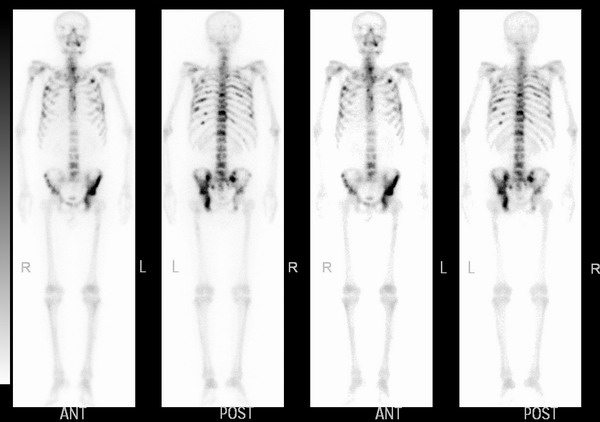

乳腺癌术后骨转移一例姑息性骨转移灶放疗

(18)f-fdg pet和 (99)tc m-mdp骨扫描对乳腺癌骨转移诊断价值的meta

骨转移图片

骨扫描骨转移报告图

肺癌骨转移骨扫描图片

骨扫描显示骨转移图片